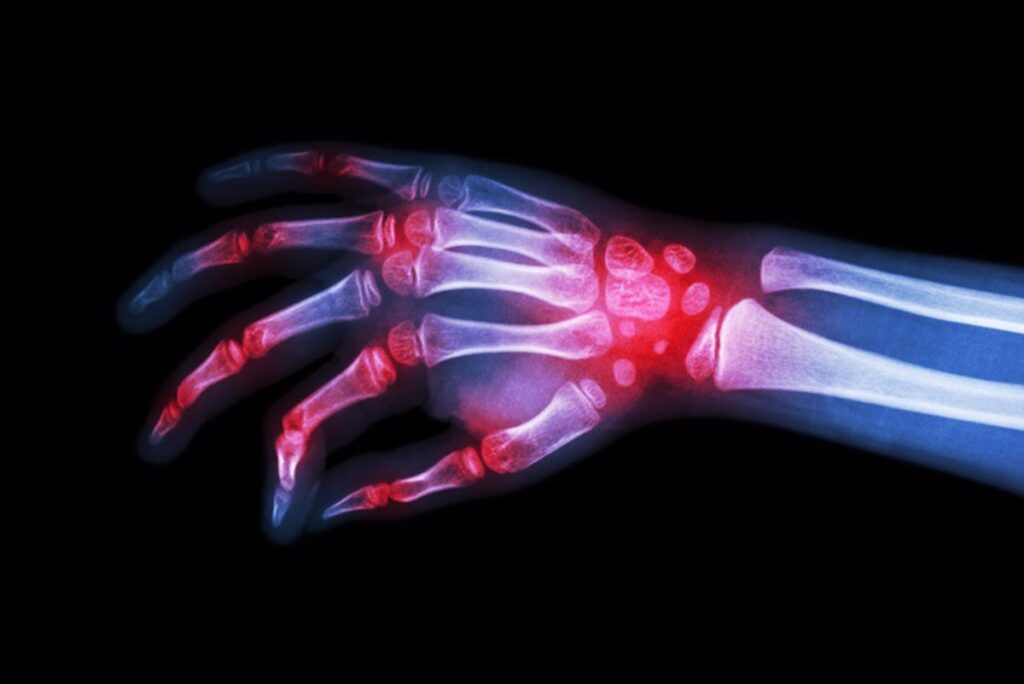

Las enfermedades reumáticas son la primera causa de incapacidad física y la segunda causa de absentismo laboral en los países occidentales, y es que son responsables del 24 por ciento de las incapacidades temporales y del 50 por ciento de las permanentes, según datos de la Organización Mundial de la Salud (OMS).

Tras ello, ha recordado que en España hay 11 millones con este tipo de afecciones, que son la principal causa de jubilación por enferemdad y supone “un gran coste” a nivel sociosanitario, emocional y personal, según un comunicado de la SER.